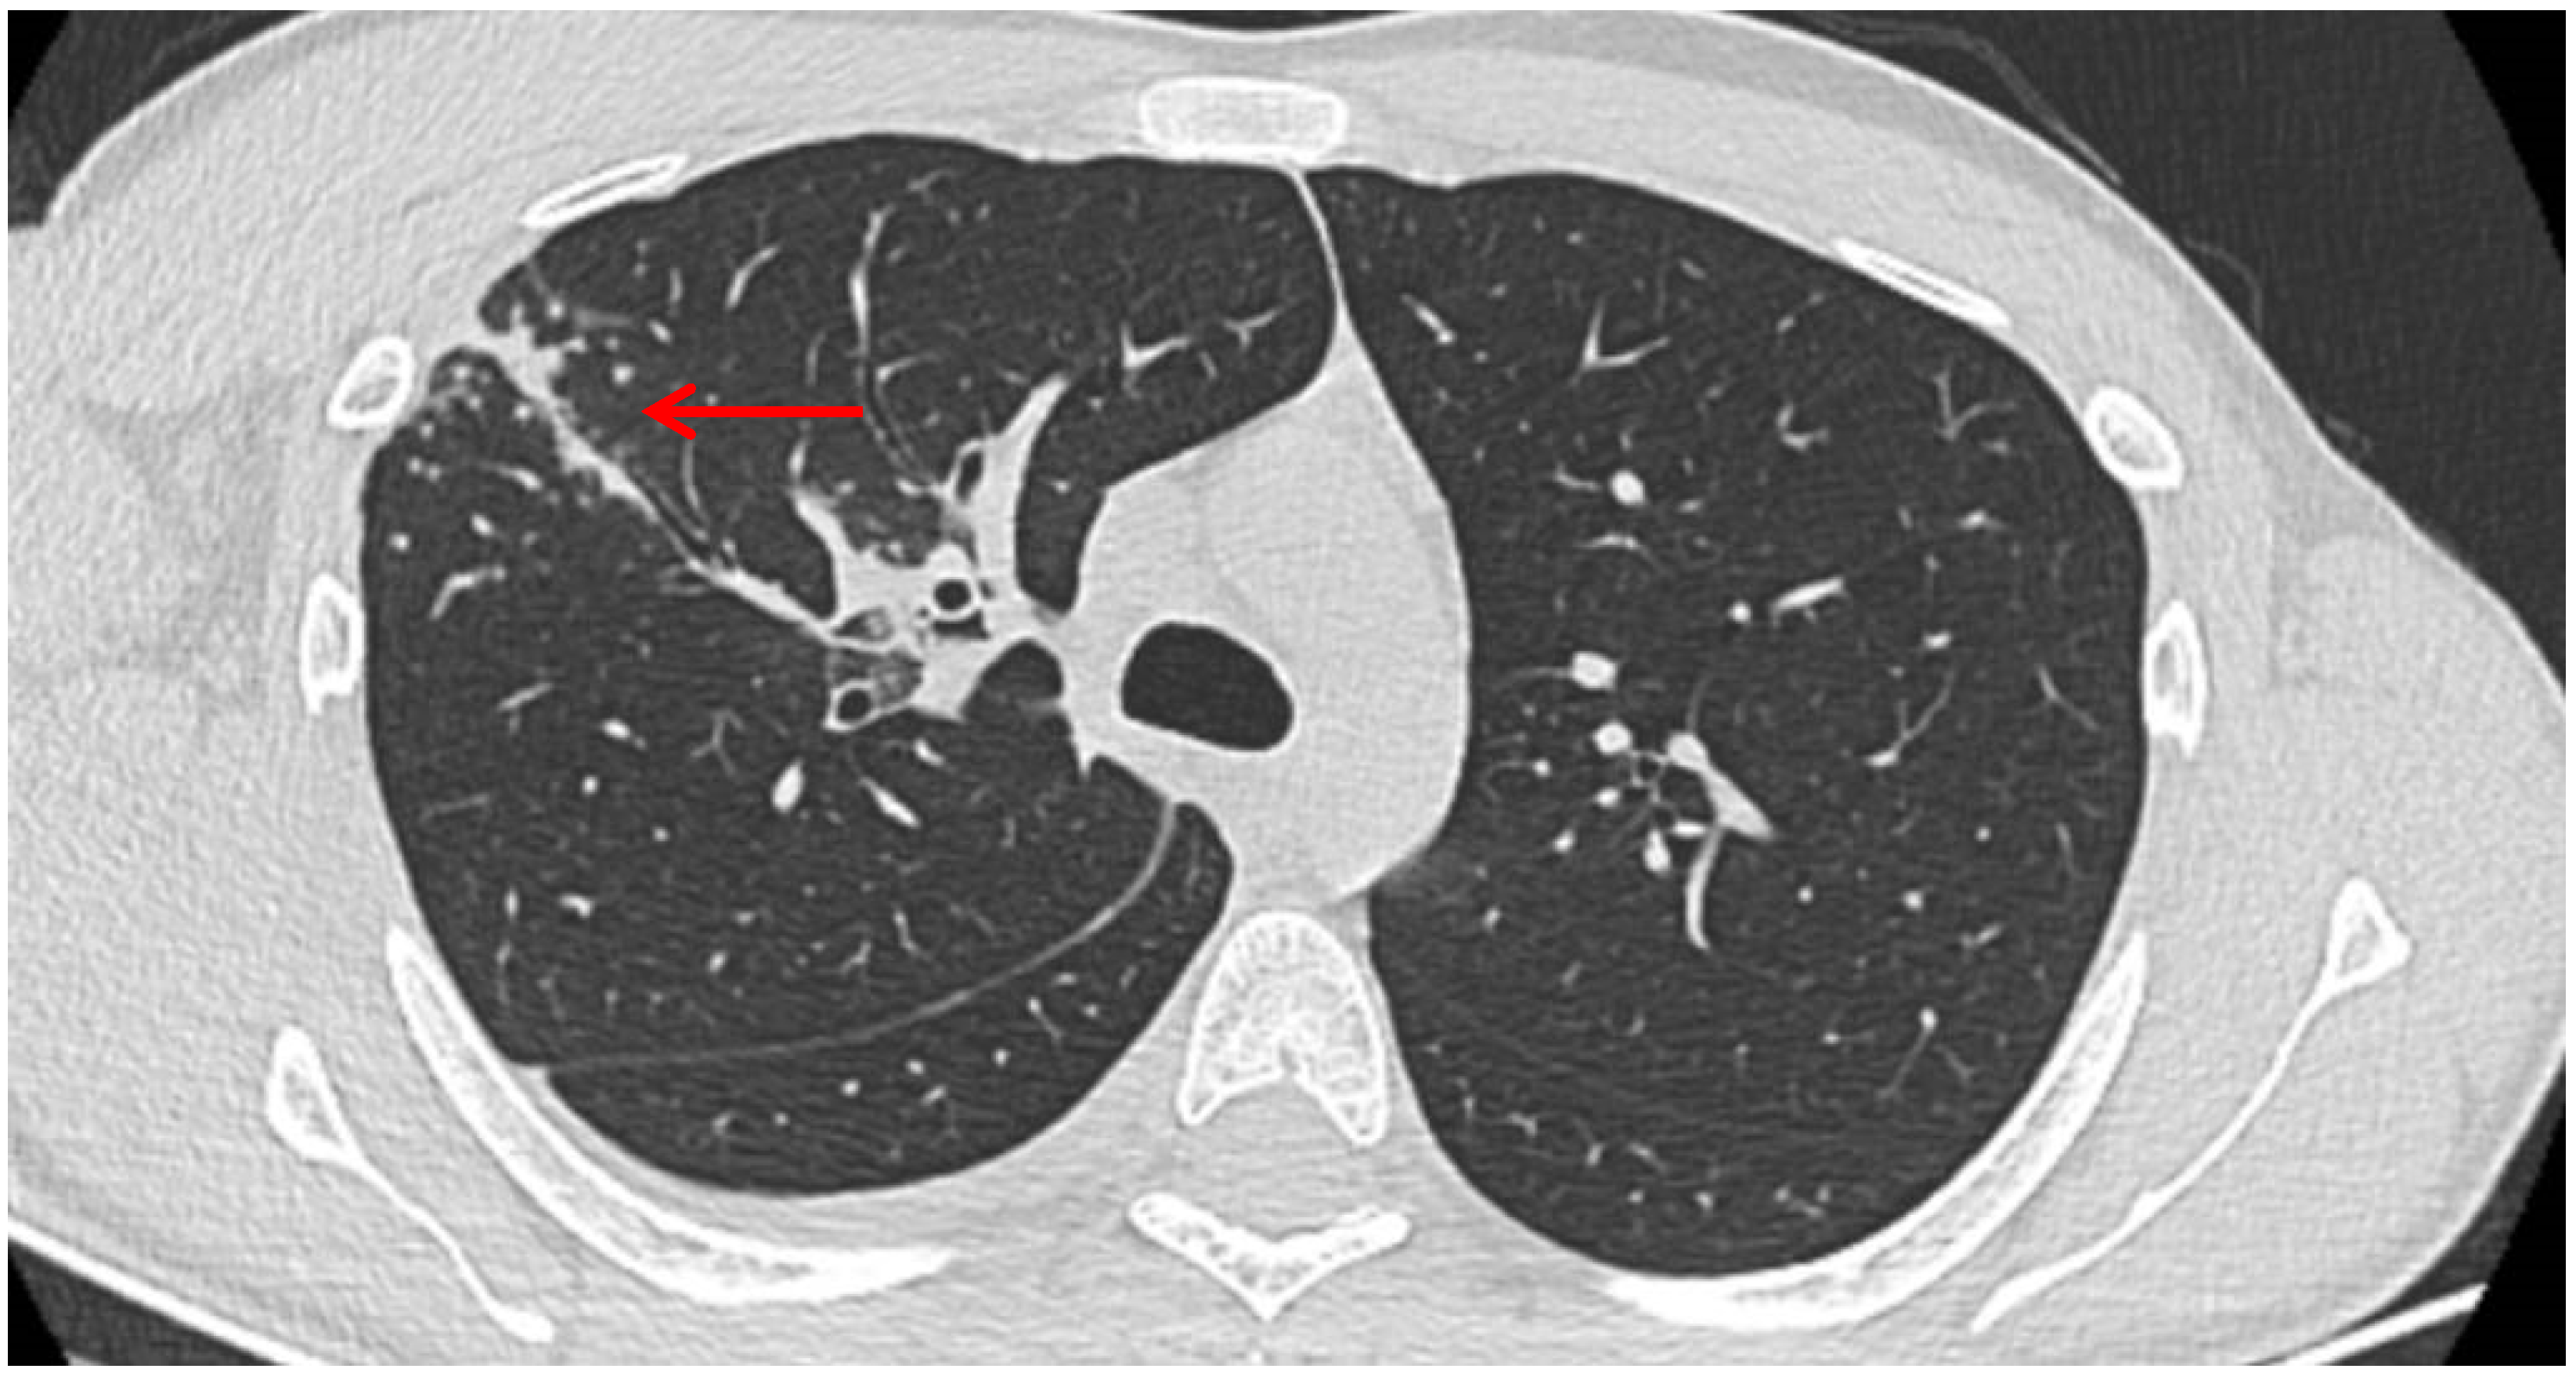

A posteroanterior chest radiography (chest X-ray) before admission revealed a high-intensity opacity with indistinct margins and a heterogeneous appearance, localized in the right suprahilar region (Figure 1). Subsequent native and contrast-enhanced chest computed tomography scans (CT) identified centrilobular micronodules and consolidations associated with linear lesions that showed a characteristic “tree-in-bud” pattern in the right upper lobe, along with fluid accumulation in the right pleural cavity, suggestive of secondary pulmonary TB or other infectious ethiology (Figure 2).

Figure 2. Lesions that showed a characteristic “tree-in-bud” pattern in the right upper lobe, along with fluid accumulation in the right pleural cavity (red arrow).